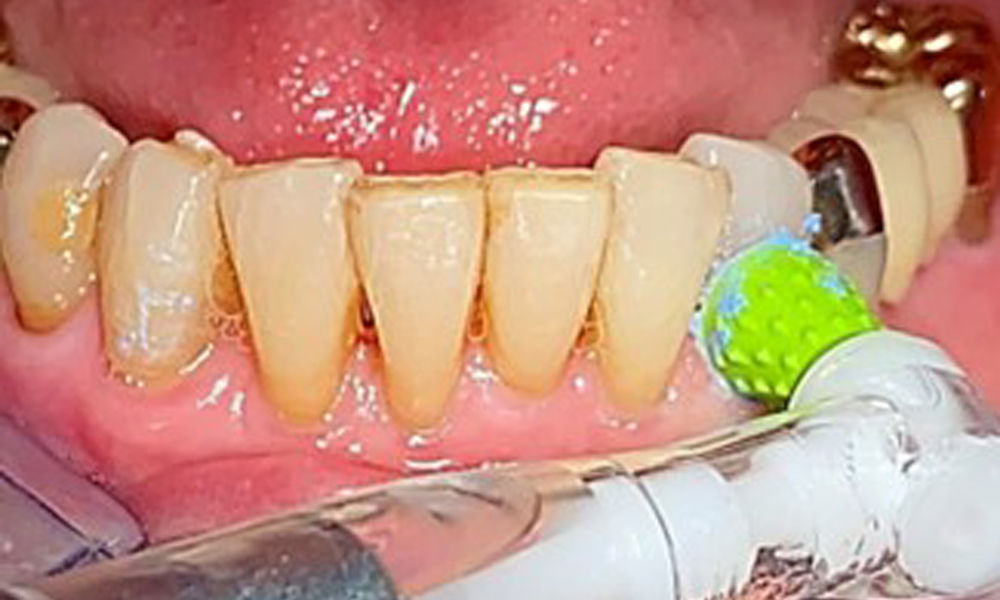

Für die Restaurationsränder und Zahnzwischenräume und Implantatoberflächen kann das Pulverstrahlgerät mit einem niedrig-abrasiven Pulver zum Einsatz zur Entfernung von Biofilm kommen (Abb. 12). Durch selektives Polieren (Abb. 13) sollte eine Glättung aller weniger sensiblen Bereiche erfolgen, da die bakterielle Wiederanhaftung reduziert wird. (9)